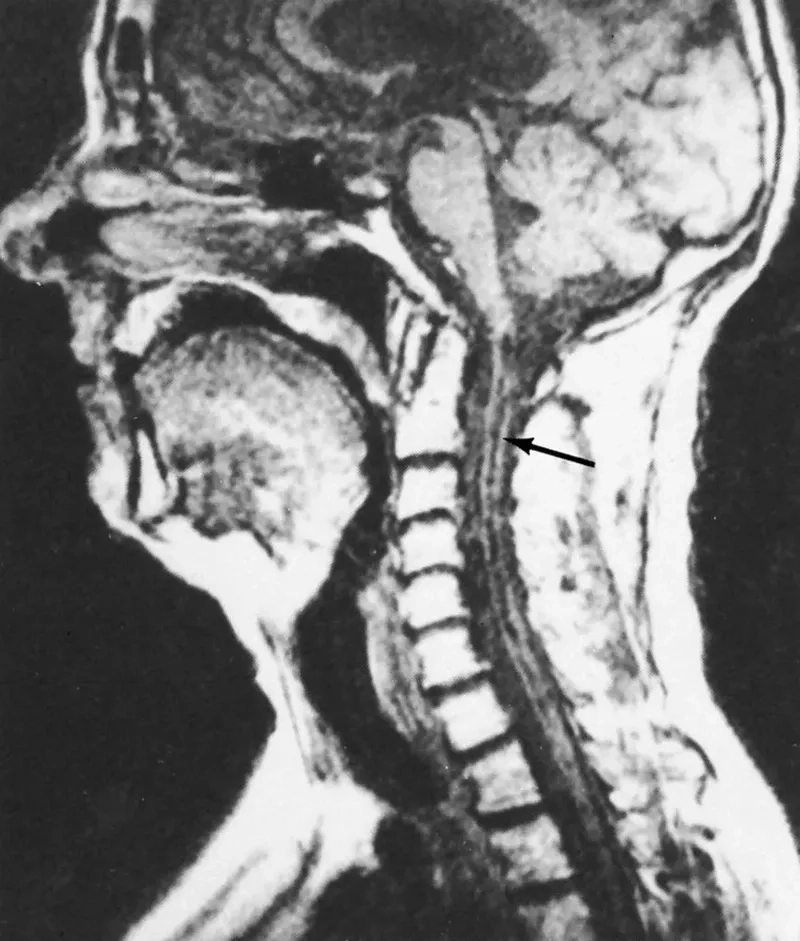

• The most frequent of the causes of syringomyelia is a Chiari malformation, where brain tissue extends into the spinal canal, obstructing fluid flow.

• This blockage forces fluid into the spinal cord, creating a fluid-filled cyst, known as a syrinx, which can expand and damage nerve tissue.

• Regular monitoring with MRI scans is essential to track the size and progression of the syrinx and determine the best timing for surgical intervention.